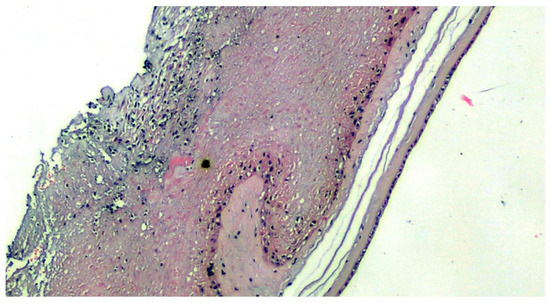

Figure 1.

COVID-19-positive mother placenta. Terminal chorionic villi with poor vascular component (distal hypoplasia of the villi due to early maternal malperfusion) with increased syncytial nodes. Some villi show a deposition of fibrin in the intervillar space with progressive reduction of the villi (H&E, Hematoxylin and Eosin, 100×).